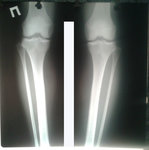

Рентген в процессе коррекции

Вложения